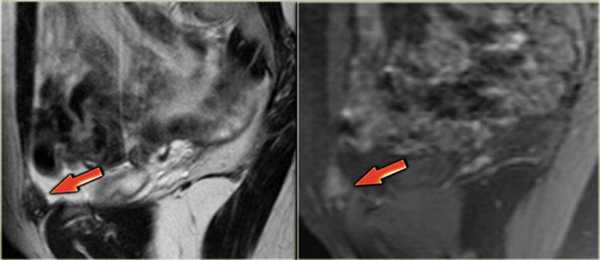

Покажет ли МРТ эндометриоз? На Т2 взвешенных сагиттальных МР-томограммах визуализируются два патологических веерообразных участка, дающих гипоинтенсивный сигнал (красные стрелки). Эти изменения типичны для эндометриоза с инфильтрацией стенки кишечника. Также определяется подслизистый отек, характеризующийся гиперинтенсивным сигналом со стороны отделов стенки кишки, расположенных ближе к просвету

Эндометриоз на МРТ малого таза. В случае циркулярного поражения эндометриоидная инфильтрация может приводить к сужению просвета кишечника. У пациенток при этом возможно изменение формы каловых масс (они становятся узкими в виде «карандаша») либо запоры. На Т2 взвешенных сагиттальных МР-томограммах определяется стеноз прямой кишки на ограниченном участке вследствие циркулярной инфильтрации